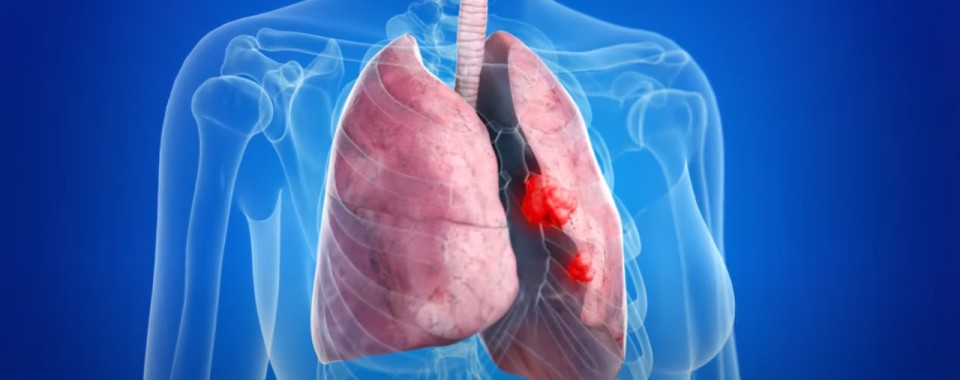

폐렴 증상 폐렴은 폐의 세균, 바이러스, 곰팡이 등 감염으로 인해

폐포(폐 속의 공기 주머니)에 염증이 생기고, 고름이나 액체가 차는 질환입니다.

폐렴 증상 4. 흉통(가슴 통증)

- 폐렴으로 인한 염증이 흉막까지 퍼지면 날카로운 가슴 통증이 발생